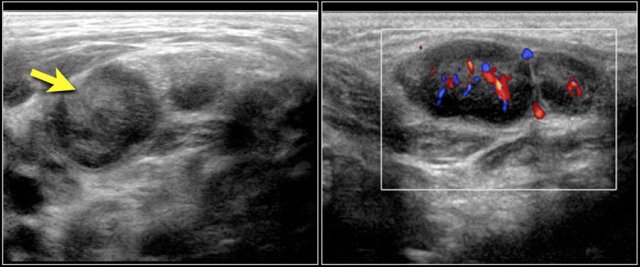

The images are of a fourteen-year-old boy with a painless swelling in the left neck.

The ultrasound shows several enlarged hypoechoic lymhnodes, that lack an hyper-echoic hilum.